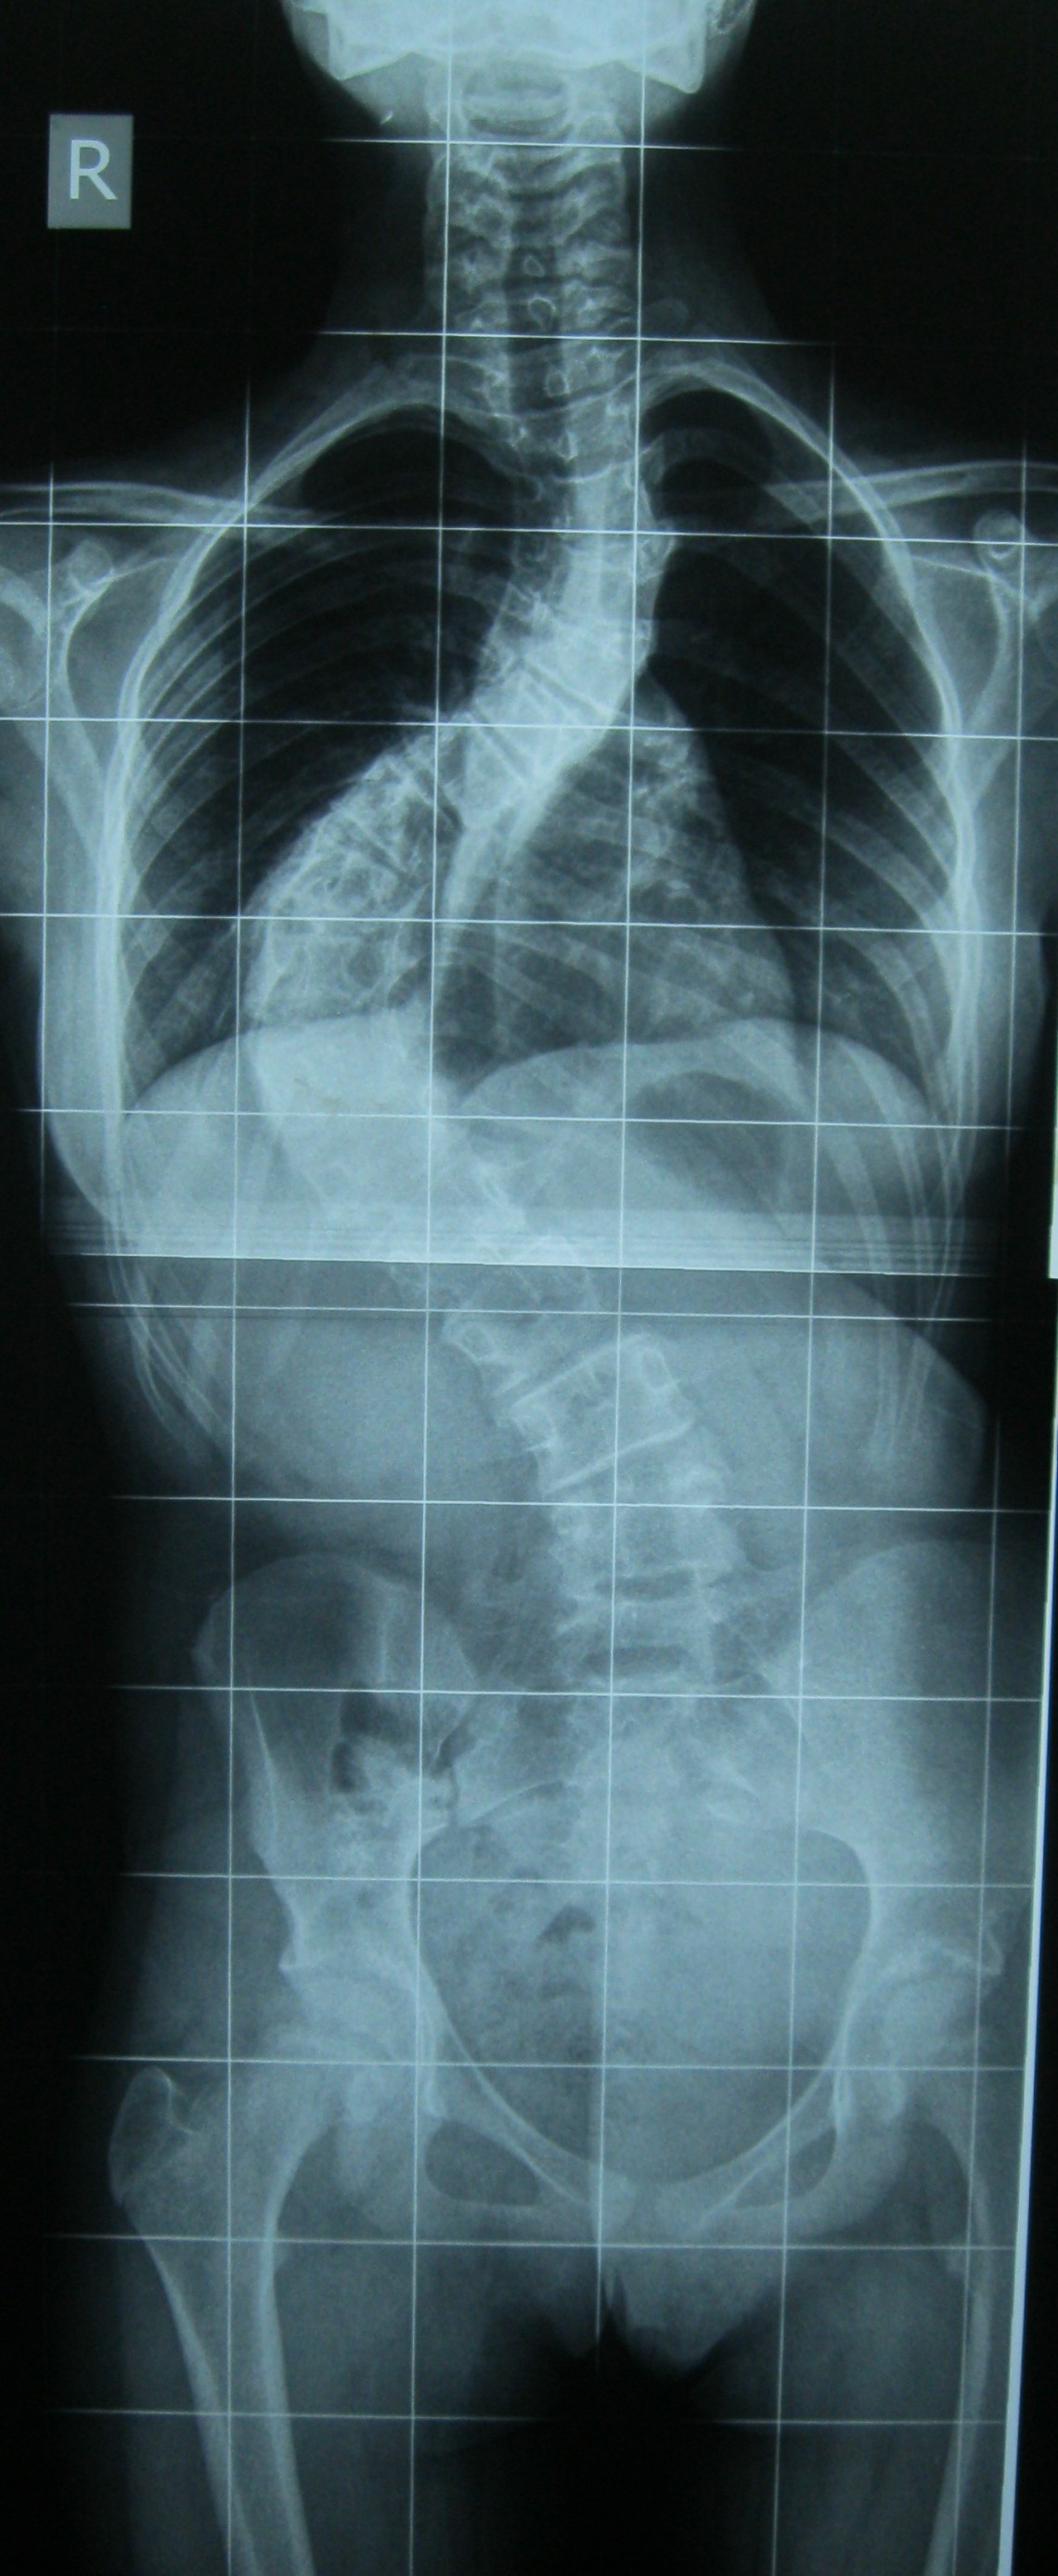

Farklı tipte skolyozu olan hastaların ameliyat öncesi ve sonrası fotoları: